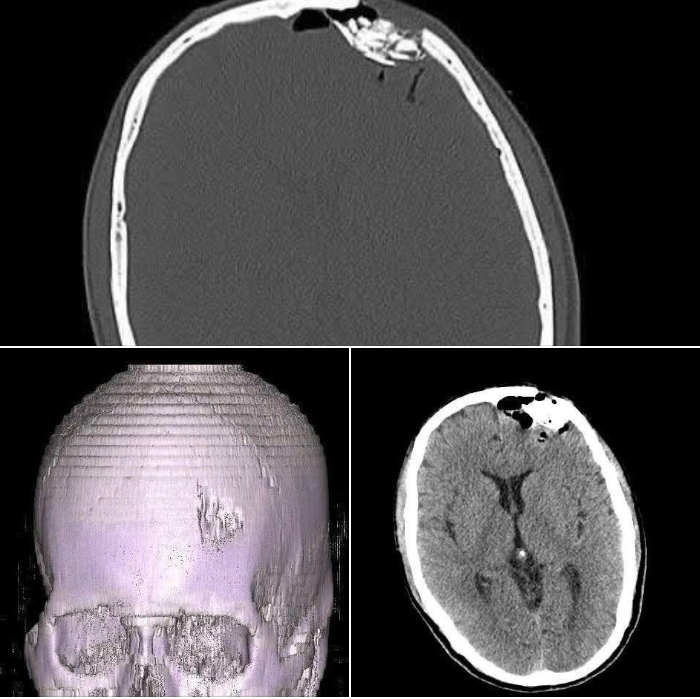

Chẩn đoán hình ảnh cho thấy: Vỡ lún xương trán; Tổn thương mô não kèm dị vật trong vết thương.

Hình ảnh xương sợ bị vỡ lún, chảy máu - Ảnh BVCC

Ê-kíp khoa Ngoại Thần kinh đã tiến hành phẫu thuật cấp cứu: Lấy bỏ dị vật và mảnh xương vỡ lún; Xử lý tổn thương não và khâu phục hồi màng cứng